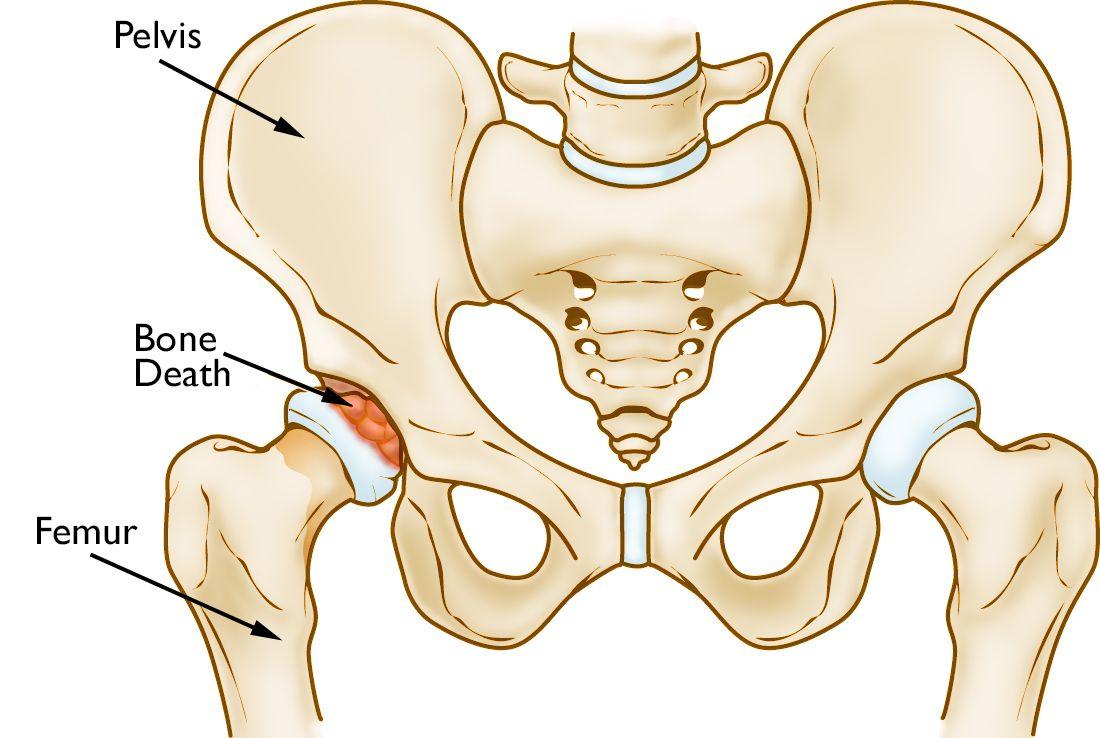

髋骨坏死发生在股骨头,它是髋关节球窝关节的球体。

当股骨头的血液供应中断时,会发生髋骨坏死。如果没有足够的营养,股骨头的骨头就会死亡并逐渐塌陷。结果,覆盖髋骨的关节软骨也会塌陷,导致关节炎。

在骨坏死中,股骨头中的骨头会慢慢死亡。